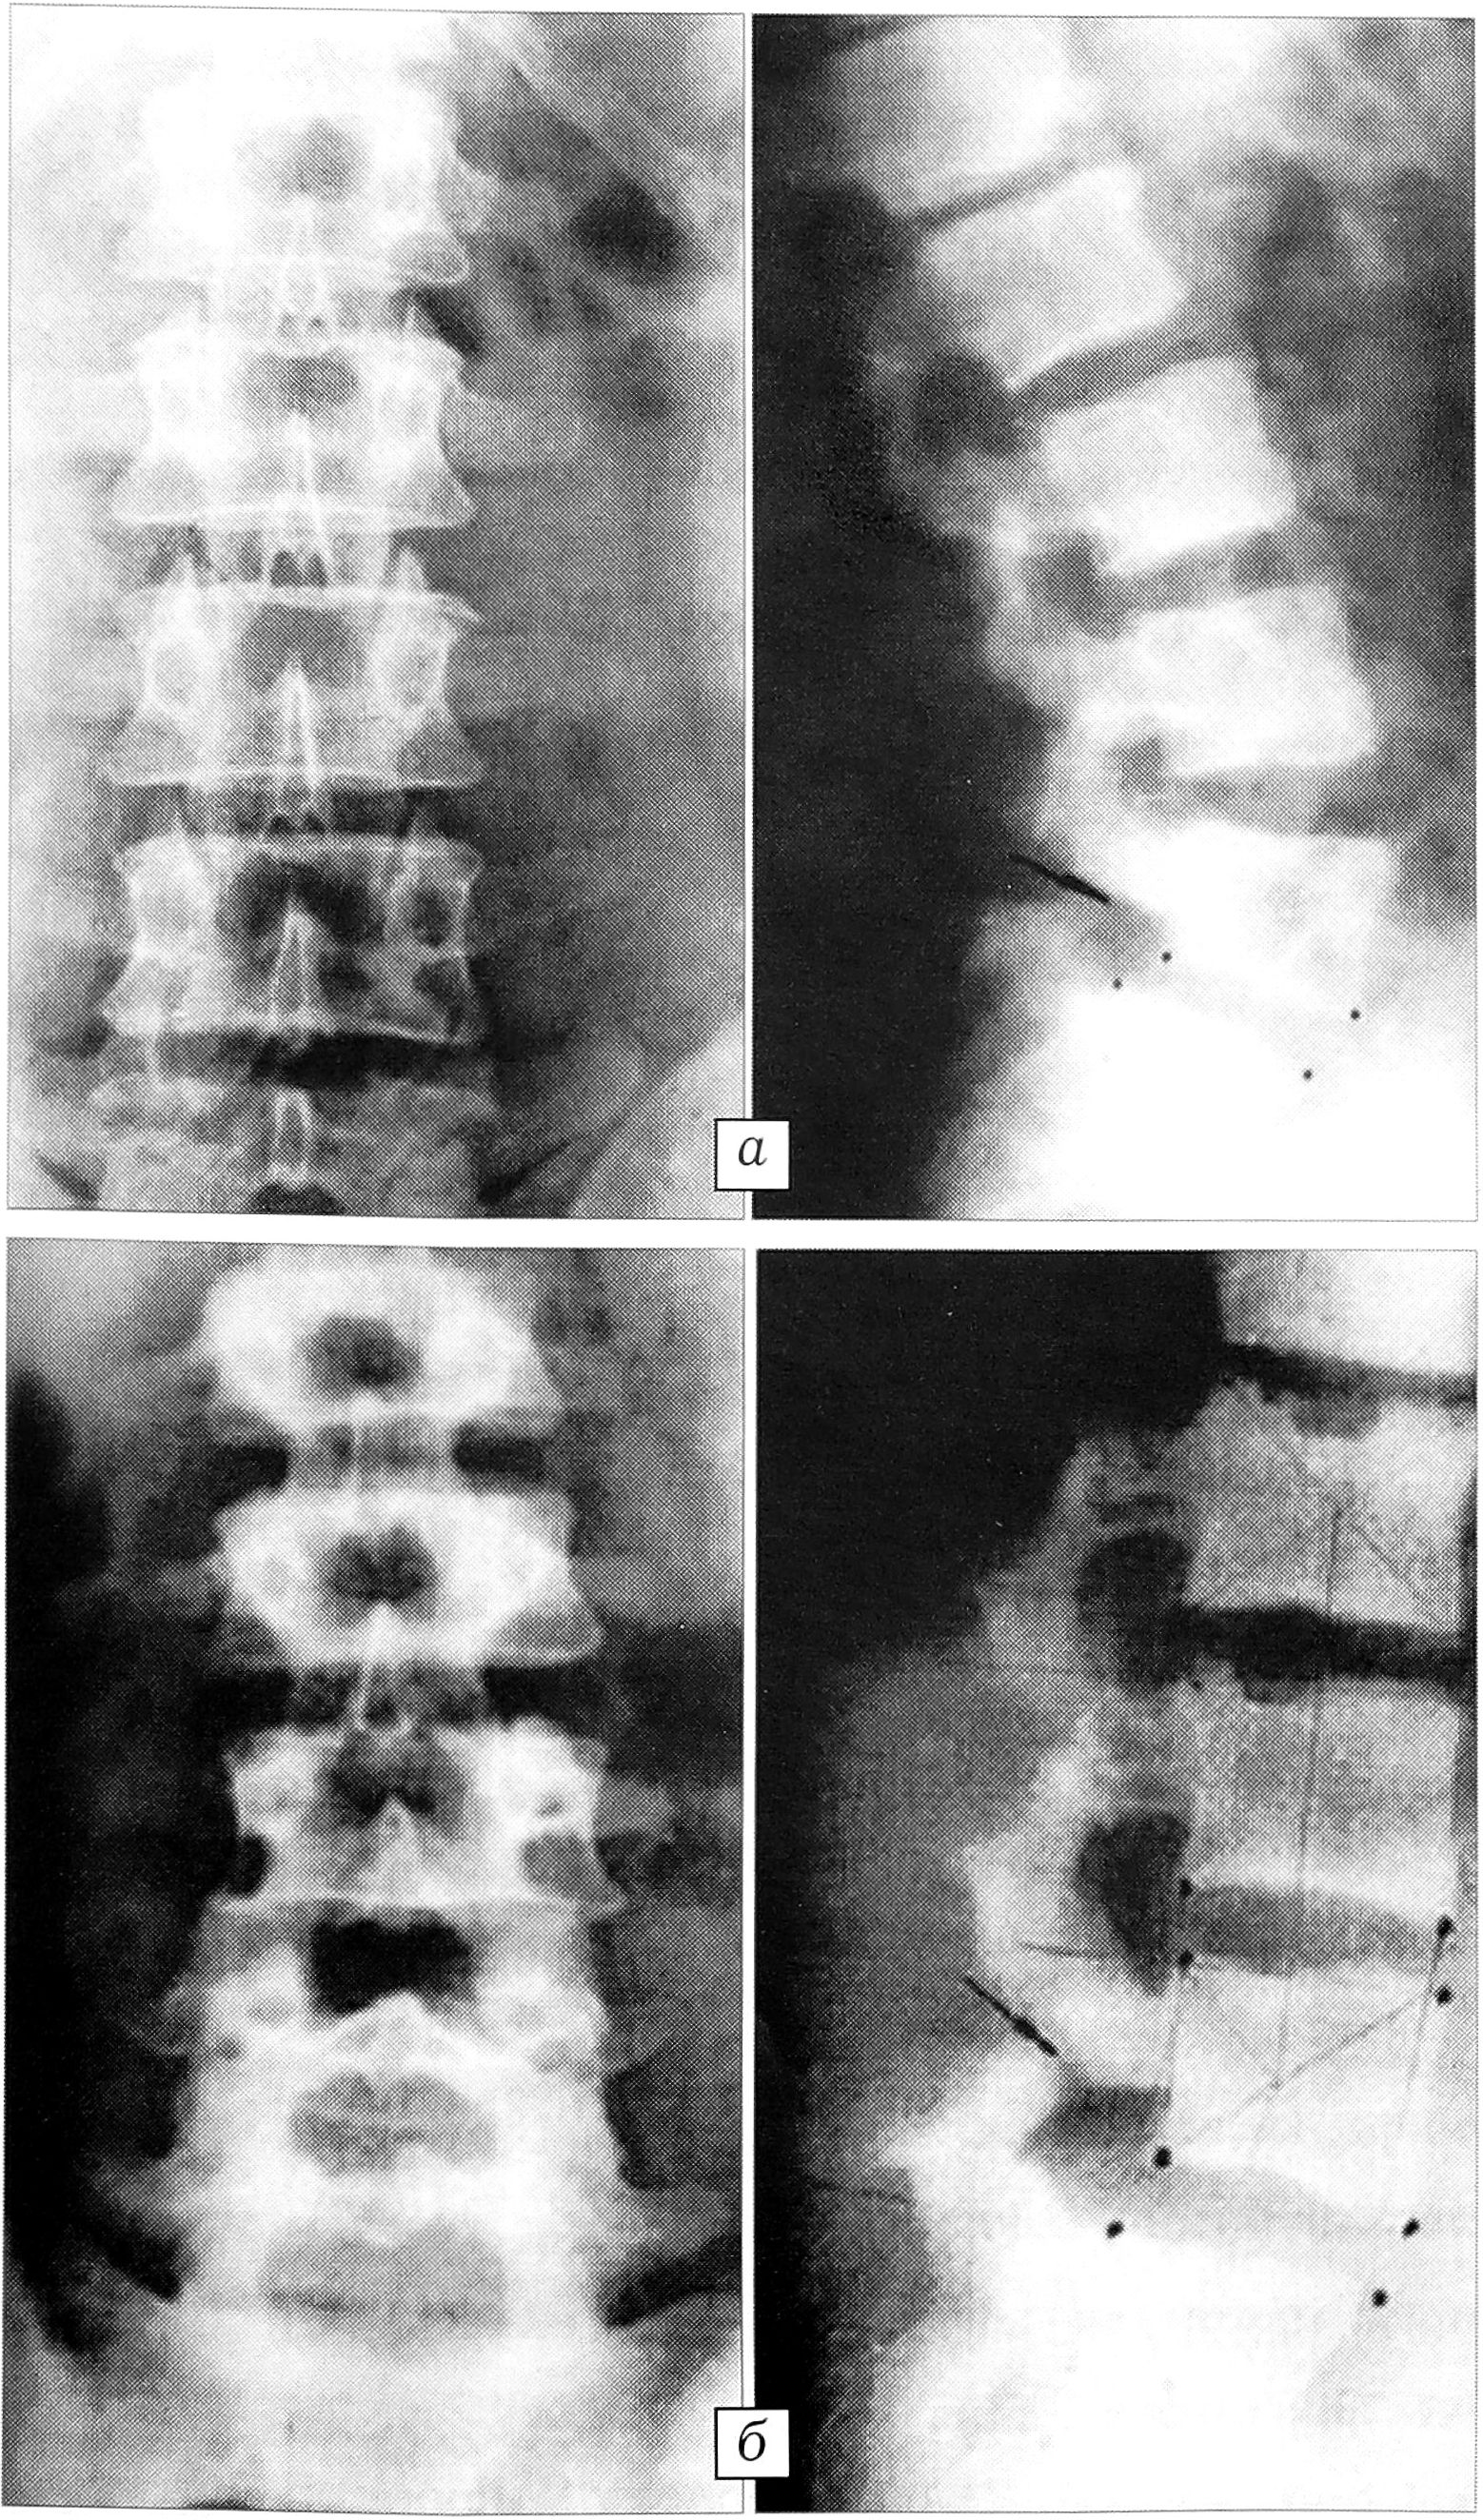

В межпозвонковом диске продолжающаяся компенсаторная гиперпродукция основного вещества матрикса, а также недостаточность трофических систем (в частности нарушение регуляции онкотического давления) сопровождаются значительным повышением внутридискового давления. На этом фоне снижение жесткости фиброзного кольца, связанное с нарушением структуры и дезагрегацией его коллагеновых и неколлагеновых протеиновых комплексов, проявляется тангенциальными расслоениями и радиальными трещинами пластин. В дальнейшем при действии биомеханического фактора возникают разрывы фиброзного кольца, причем эти разрывы вследствие высокого внутридискового давления, как правило, сопровождаются пролапсом вещества студенистого ядра. В зависимости от локализации выпавшего фрагмента формируется клиническая симптоматика внутридисковых перемещений студенистого ядра, протрузии или экструзии межпозвонкового диска (рис. 6, а).

Качественно иной путь фактического отказа наблюдается при нарушении процессов гидратации—дегидратации матрикса со сдвигом в сторону дегидратации. Такая ситуация связана с уменьшением длины молекулярных цепей ГАГ [19] и снижением их способности к агрегации [15], что делает возможным их вымывание из матрикса с циркулирующей жидкостью [18]. Продукты деградации основного вещества включаются в надмолекулярные агрегаты протеогликанов и ускоряют деполимеризацию [10], делая их доступными для каталитических ферментов [12]. Все эти изменения резко снижают гидратацию тканей межпозвонкового диска. Формируется механическая неполноценность студенистого ядра, снижающая его опорно-абсорбционную функцию, с развитием нестабильности ПДС и возникновением болевого синдрома (рис. 6, б).

Рис. 6. Дезадаптация в системе позвоночного двигательного сегмента: а — при гипергидратации матрикса студенистого ядра (внутридисковые перемещения ядра L3-4 межпозвонкового диска, экструзии L4-5, L5-S1 дисков); б — при дегидратации матрикса студенистого ядра (нестабильность L3_4, L4_5 сегментов).